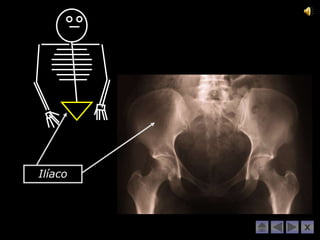

Ilíaco

Ilíaco Muito bem!!! Carpo e Metacarpo Coluna Vertebral Falanges da mão Tíbia e Perónio Úmero e Clavícula Tarso e Metatarso Rótula Rádio e Cúbito Crânio Falanges do pé Fémur Externo e Costelas